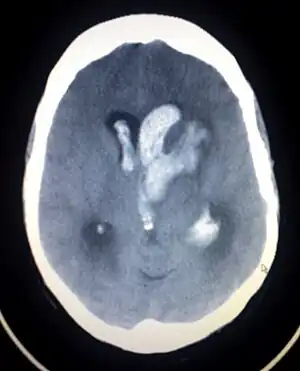

| Axial CT scan of a spontaneous intracranial hemorrhage | |

Intracranial hemorrhage (ICH), also known as intracranial bleed, is bleeding within the skull.[1] Subtypes are intracerebral bleeds (intraventricular bleeds and intraparenchymal bleeds), subarachnoid bleeds, epidural bleeds, and subdural bleeds.[2] More often than not it ends in a lethal outcome.